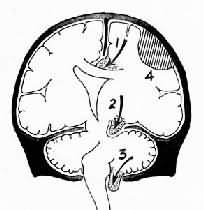

图16-6 脑疝模式图 1.扣带回疝;2.海马钩回疝;3.小脑扁桃体疝;4.硬膜外血肿 2.小脑天幕疝又称海马钩回疝。位于小脑天幕以上的额叶或颞叶内侧的肿瘤、出血、梗死等病变引起脑组织体积肿大,导致颞叶的海马钩回经小脑天幕孔向下膨出。海马钩回疝可导致以下后果:①同侧动眼神经在穿过小脑天幕裂孔处受压,引起同侧瞳孔一过性缩小,继之散大固定,及同侧眼上视和内视障碍。②中脑及脑干受压后移,可导致意识丧失;导水管变狭,脑脊液循环受阻加剧颅内压的升高;血管牵伸过度,引起中脑和桥脑上部出血梗死,可导致昏迷死亡。③中脑侧移,使对侧中脑的大脑脚抵压于该侧小脑天幕锐利的游离缘上,形成Kernohan切迹。严重时该处脑组织(含锥体索)出血坏死,导致与天幕上原发病变同侧的肢体瘫痪,引起假定位症。④压迫大脑后动脉引起同侧枕叶距状裂脑组织出血性梗死(图16-7)。